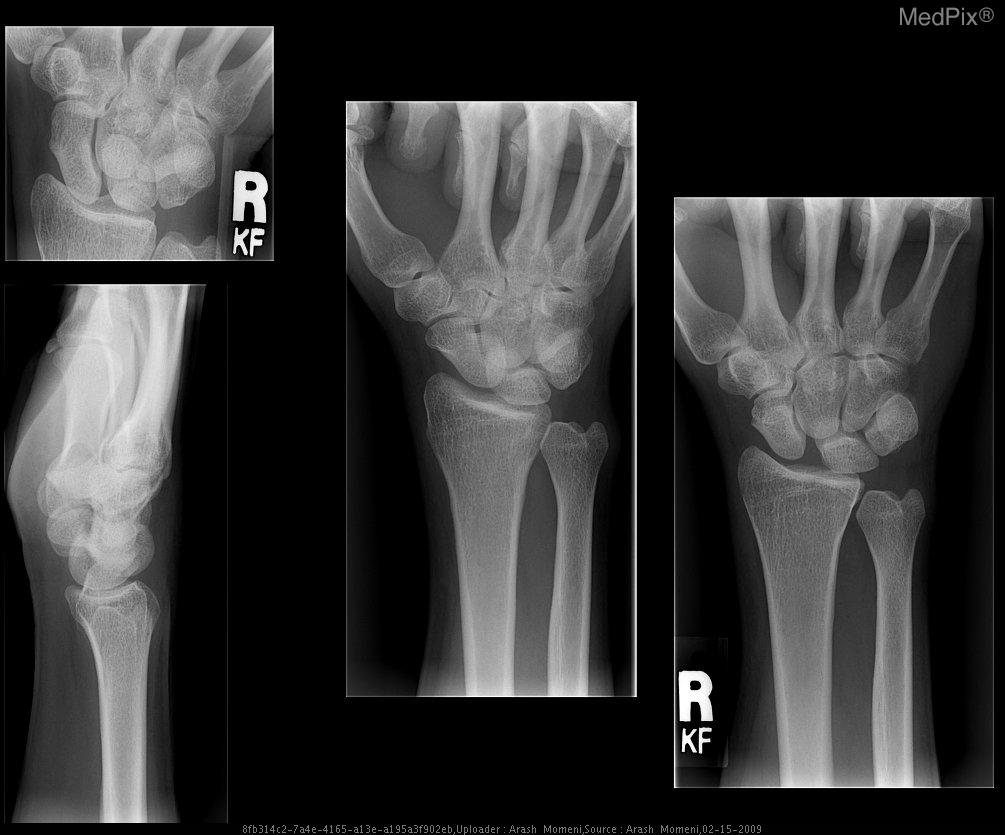

Distal radioulnar joint dislocation is an uncommon injury where the distal radius and ulna lose alignment, often caused by trauma, falls, or sports injuries. Patients typically present with wrist pain, swelling, deformity, and difficulty rotating the forearm. Diagnosis is made

The DRUJ compression test evaluates for pathology at the distal radioulnar joint. With the forearm in a neutral position, the examiner compresses the ulna against the radius. The test evaluates for instability, tenderness, crepitus, or swelling and is compared to the